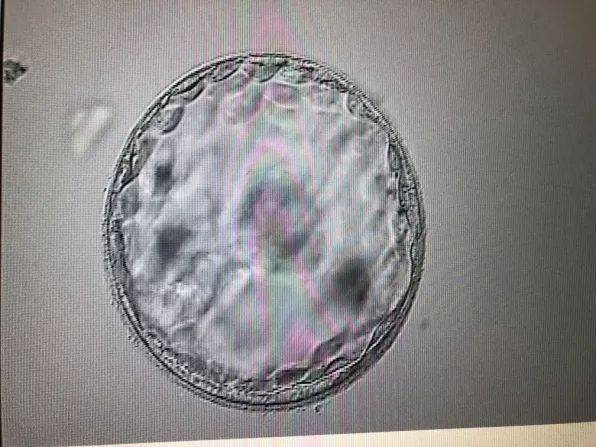

在生物学领域,为什么后壁生儿子多的现象与Y染色体的遗传特性密切相关。男性胎儿携带Y染色体,女性胎儿携带X染色体。当男性精子的Y染色体与卵细胞的X染色体结合时,就会形成XY组合,从而产生儿子;而当X染色体与X染色体结合时,则会形成XX组合,产生女儿。

据研究,男性精子的活动性普遍高于女性精子,且在受精过程中,Y染色体精子具有更高的竞争力。此外,Y染色体精子在进入卵细胞后,会与X染色体精子争夺与卵细胞核融合的机会。因此,在竞争中,Y染色体精子更容易胜出,从而导致了为什么后壁生儿子多的现象。